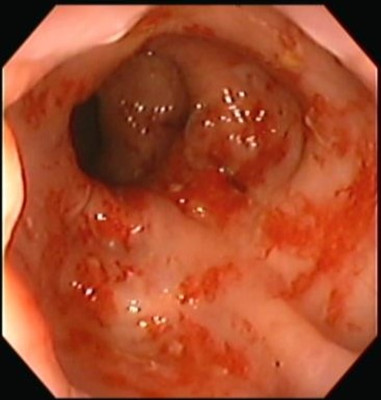

Proctitis

Envíado por Dr. Carlos Ernesto Arévalo